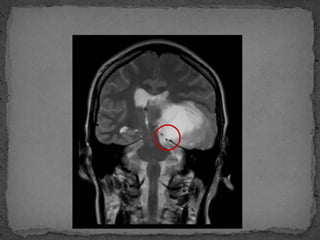

 IRM :

 Signe indirect de HTICB

 Arachnoidocéle

 Tige pituitaire baignant dans la selle turcique

 Aspect en croix ou en T du chiasma et tige pituitaire baignant dans

la selle turcique